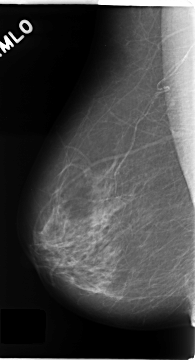

C_0135_1.RIGHT_CC

RIGHT_CC LINES 4704 PIXELS_PER_LINE 2408 BITS_PER_PIXEL 12 RESOLUTION 50 NON_OVERLAY

RIGHT_MLO LINES 4672 PIXELS_PER_LINE 2528 BITS_PER_PIXEL 12 RESOLUTION 50 NON_OVERLAY